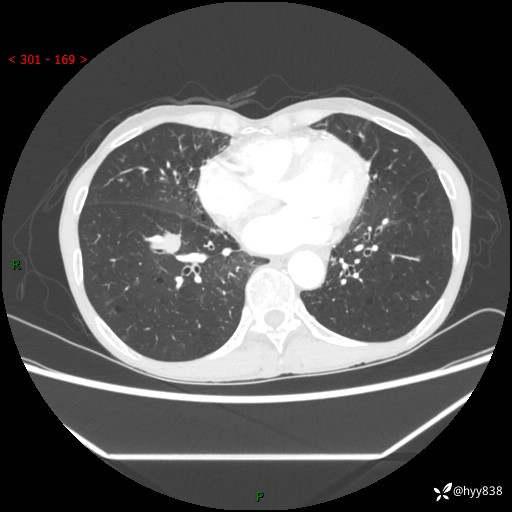

【现病史及既往史】:患者3天余前因既往肺气肿复查胸部CT发现“右肺下叶结节、双肺多发结节、双肺门及纵膈淋巴结增大”,平素偶有咳白色粘液痰,下肢乏力,无明显低热、盗汗、咯血、胸痛、喘气等不适,今为求明显结节性质遂来我院门诊就诊,门诊以“孤立性肺结节”收治入院。 起病以来,患者精神饮食睡眠一般,大小便正常,体力无明细变化,体重近年来较前下降。

【检查】:胸部CT增强